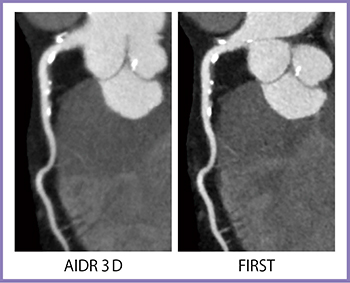

1.心血管

冠動脈CTAでは,AIDR 3DよりもFIRSTの方が石灰化や壁在血栓が明瞭に描出される(図3)。そして,驚くべきはステントの分解能で,FIRSTのCardiac Sharpで再構成を行うと,ストラットまで分離して描出される(図4)。頸動脈ステントの3D画像では,ステントのメッシュ構造まで観察することができる(図5)。

図3 冠動脈CTA